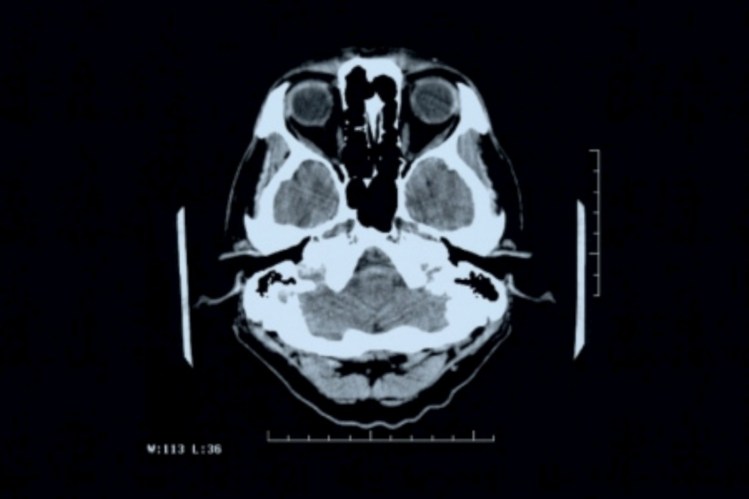

El KMO es una enzima que se produce en el cerebro y las células inmunes pueden estar asociados con el proceso de inflamación. La actividad de esta enzima produce los compuestos que tienen un efecto negativo sobre el sistema nervioso y son parte de las enfermedades neurodegenerativas tales como la enfermedad de Alzheimer, corea de Huntington o la enfermedad de Parkinson.

Un equipo dirigido por Nigel Scrutton de la Universidad de Manchester, Reino Unido, logró tomar una foto de esta proteína en tres dimensiones utilizando la técnica de la cristalografía de rayos X. Por lo tanto, se convirtió en la forma conocida de la proteína. Este dato es importante porque ahora se puede saber donde se unen las sustancias que inhiben la KMO.